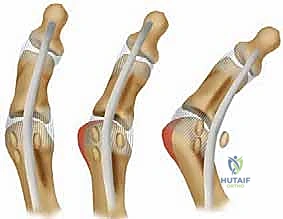

هنا يبرز سؤال هام: هل يتم استئصال العظمة السمسمية المكسورة (Sesamoidectomy) أم تثبيتها (Internal Fixation)؟

تاريخياً، كان الاستئصال هو الحل الشائع. لكن الأستاذ الدكتور محمد هطيف يتبنى المدرسة الحديثة التي تؤكد على ضرورة الحفاظ على العظمة السمسمية متى ما كان ذلك ممكناً عبر التثبيت الداخلي. استئصال العظمة يؤدي إلى خلل دائم في ميكانيكا القدم، يضعف قوة الإبهام بنسبة تصل إلى 30%، ويزيد من خطر تشوه إصبع القدم المطرقية (Cock-up toe deformity).